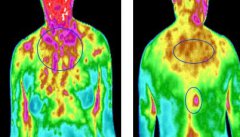

红外扫描早期预警预防乳腺癌

王总拼搏这么多年对自己的身子还是非常关注的,马上就咨询了医生,在医院了解了她的身体状况以后,建议做一个GTT医用红外热像仪的扫描检查,这样对自己身体会更加了解

红外热像仪最基本的工作原理我们可以理解成检测一个物体本身散发出的红外辐射,把物体表面的温度根据色彩的不同分布成图像,而身体的温度越高在图像中呈现的颜色也会不同